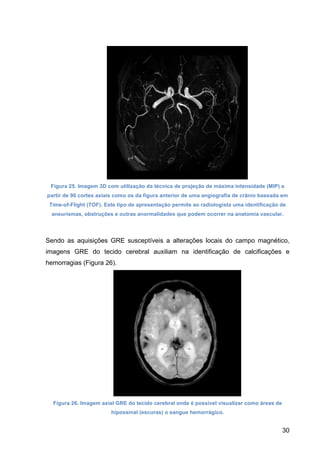

Figura 25. Imagem 3D com utilização da técnica de projeção de máxima intensidade (MIP) a

partir de 90 cortes axiais como os da figura anterior de uma angiografia de crânio baseada em

Time-of-Flight (TOF). Este tipo de apresentação permite ao radiologista uma identificação de

aneurismas, obstruções e outras anormalidades que podem ocorrer na anatomia vascular.

Sendo as aquisições GRE susceptíveis a alterações locais do campo magnético,

imagens GRE do tecido cerebral auxiliam na identificação de calcificações e

hemorragias (Figura 26).

Figura 26. Imagem axial GRE do tecido cerebral onde é possível visualizar como áreas de

hipossinal (escuras) o sangue hemorrágico.